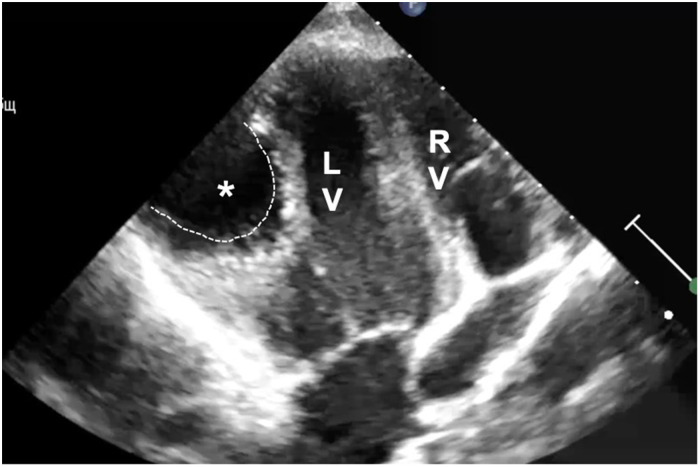

Hydatid cyst is a human parasitic disease caused by echinococcus granulosus that affects mainly the liver or the lungs but may be found in any organ, including the heart in up to 2% of the cases. Humans are infected as accidental hosts by contaminated vegetables or water and by contact with saliva from infected animals. Although cardiac echinococcosis can be fatal, it is rare and often asymptomatic in the early stage. We present the case of a young boy living on a farm who suffered from mild exertional dyspnea. He suffered from pulmonary and cardiac echinococcosis and was treated surgically through median sternotomy to prevent potential cystic rupture.